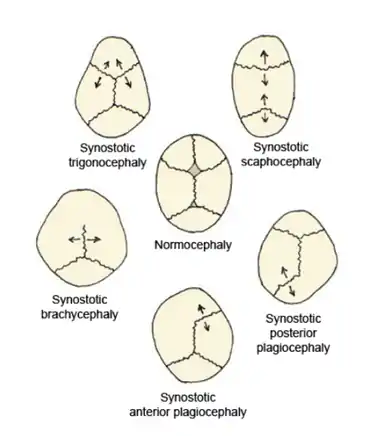

Children born with craniosynostosis have a distinct phenotype, i.e., appearance—observable traits caused by the expression of a condition's genes. The features of craniosynostosis' particular phenotype are determined by which suture is closed.[7] The fusion of this suture causes a certain change in the shape of the skull; a deformity of the skull.[7]

Virchow's law dictates that, when premature suture closure occurs, growth of the skull typically is restricted perpendicularly to the fused suture and enhanced in a plane parallel to it, thus trying to provide space for the fast-growing brain.[8] Using this law, the pattern of skull deformity in craniosynostosis often may be predicted.[8]

Scaphocephaly

An illustrative example of this phenomenon is scaphocephaly; the name providing a direct hint regarding the deformity of the skull. The literal meaning of the Greek derived word 'scaphocephaly' is boat-head. A synonymous term is 'dolichocephaly' (the prefix dolicho- means elongated).[9]

Premature sagittal suture closure restricts growth in a perpendicular plane, thus the head will not grow sideways and will remain narrow.[10][11] This is best seen in a view standing above the child looking downward at the top of the head.[12] Compensatory growth occurs forward at the coronal suture and backward at the lambdoid suture giving respectively a prominent forehead, called frontal bossing, and a prominent back portion of the head, called coning.[10][11] This is the most common form of craniosynostosis.[13]

Trigonocephaly

Trigonocephaly is a result from the premature closure of the metopic suture.[10][11] Using Virchow's law again to predict the resulting deformity, this fusion will result in a narrow forehead, which is even further emphasized by ridging of the suture.[10][11] Compensatory growth occurs at both the coronal sutures, thereby pushing the forehead forwards.[10][11] The resulting shape can best be assessed from a top view again, which will reveal a somewhat triangular form of the head.[12] Trigonocephaly is also a Greek-derived word, which can be translated as triangular-shaped head. A facial feature of metopic synostosis is hypotelorism; in the frontal view, it can be seen that the width between the eyes is smaller than usual.[11]

Plagiocephaly

The Greek word πλάγιος plágios means "skew". Plagiocephaly can be subclassified as anterior plagiocephaly or posterior plagiocephaly.

Anterior plagiocephaly

Anterior plagiocephaly is a clinical description of unilateral coronal synostosis.[10][11] Children born with unilateral coronal synostosis develop due to compensatory mechanisms a skew head; a plagiocephaly.[10][11]

Posterior plagiocephaly

Unilateral lambdoid synostosis is also called posterior plagiocephaly, indicating that this gives, just like unilateral coronal synostosis, a 'skew head'. The difference is that this time, the deformity mostly shows at the occiput.

Brachycephaly

Brachycephaly, or a 'short head', is the result of a closure of both the coronal sutures.[11] Following Virchow's law, this will result in a child's head with a restriction of growth in the forward direction and in the backward direction: recessed frontal bones and a flattened occiput.[11] Compensatory growth will occur sideways, due to the sagittal suture, and upwards, due to the lambdoid sutures.[11]